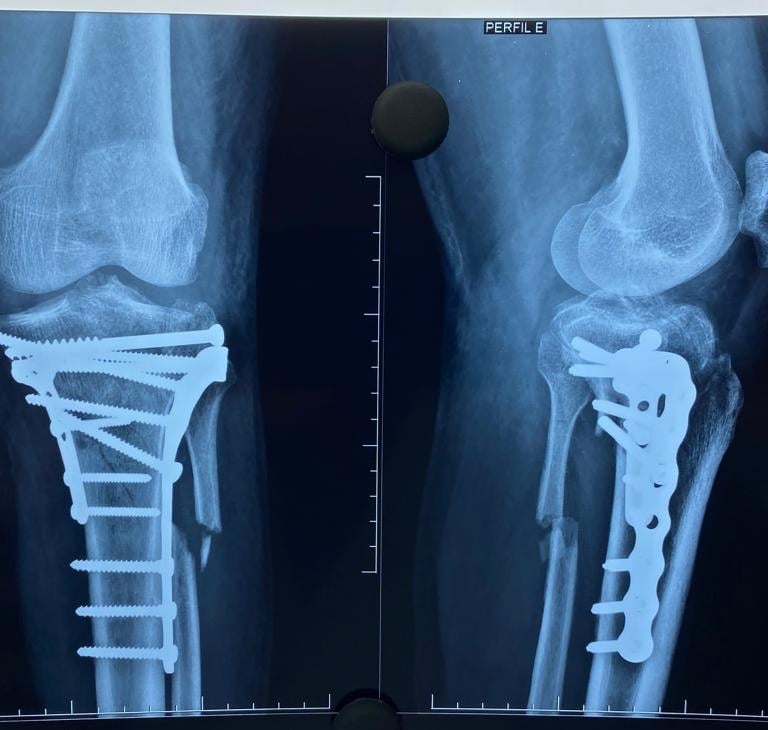

Galeria Médica

Imagens de atendimentos e procedimentos em ortopedia e traumatologia.

* Fotos autorizadas pelos pacientes para uso neste site.